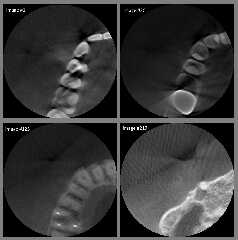

I have attached a sample of my original DICOM images (as converted to

8-bit .png) just to show what the problems are. I think that the images you are

using are of *much* higher quality.

In my opinion, my dentist needs to purchase an improved CT scanner! ;-)

Attachments:

Download 'four_sample_dicom_images_as_8_bit_png.jpg' (109 KB)

Preview of image 'four_sample_dicom_images_as_8_bit_png.jpg'